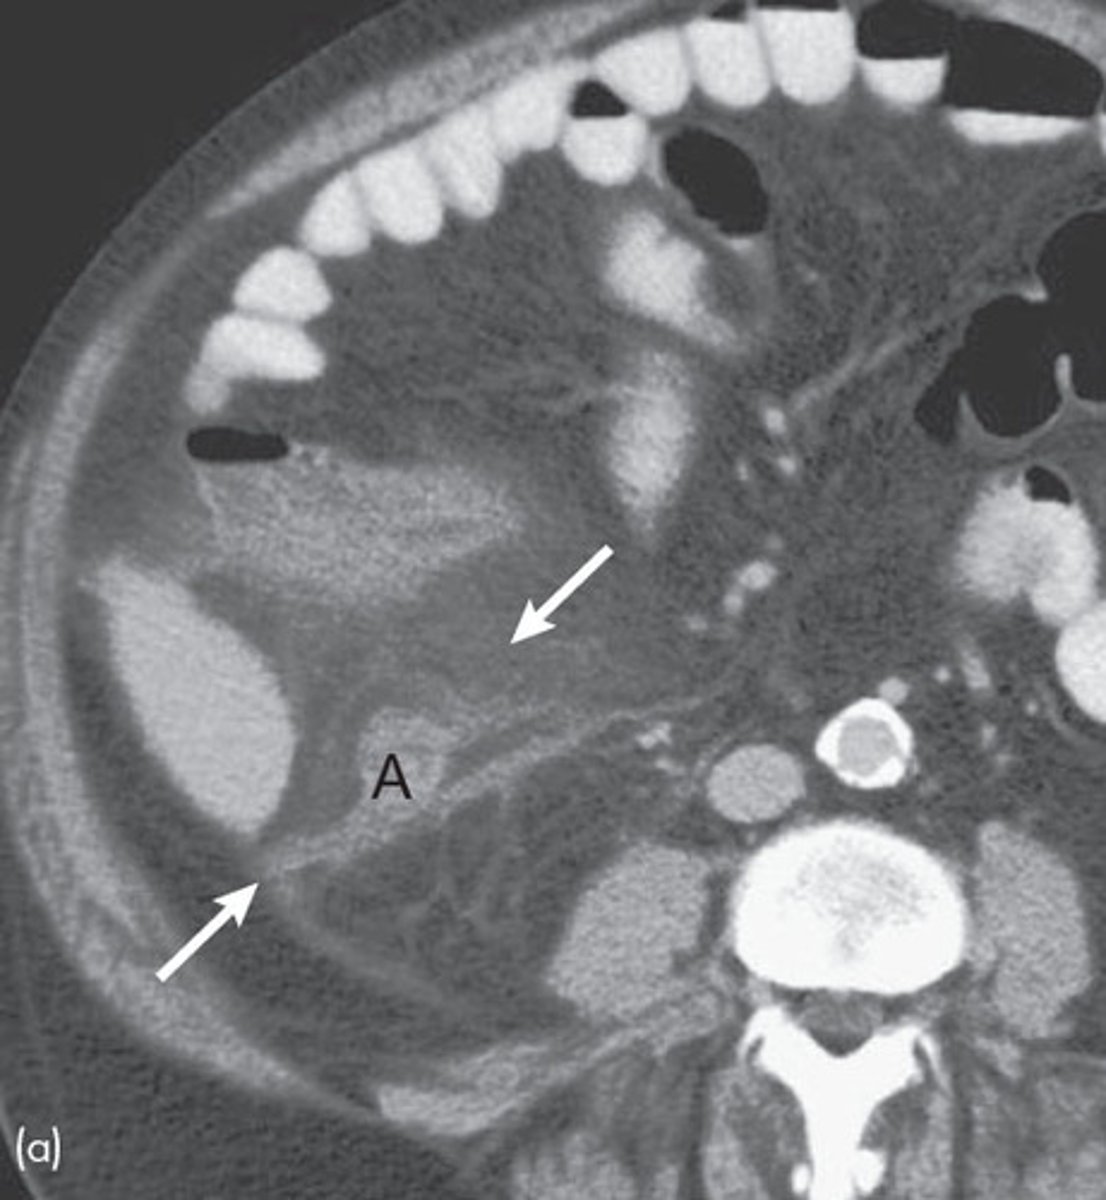

What is intestinal malrotation, & what is it often caused by?

Abnormal/incomplete rotation of the bowel during fetal development; Ladd's bands (fibrotic bands that cover parts of the small intestine)

What are the 2 major possible complications of intestinal malrotation?

Intestinal obstruction (usually due to Ladd's bands) or midgut volvulus (small bowel ischemia)

What is the best initial diagnostic test for suspected malrotation/midgut volvulus, & what must this be followed up by? What will be seen?

Initial: abdominal x-ray - double bubble sign and/or air-fluid levels (remember need to d/dx duodenal atresia from this)

Best: upper GI contrast series/contrast enema - twists of barium w/ bowel pushed over to the right